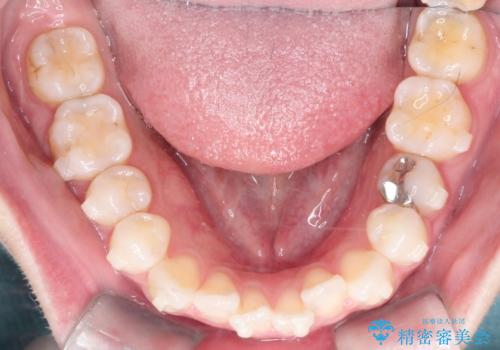

【インビザライン】がたつきをなおしたい

- 上下の前歯の凸凹が気になり、来院されました。

インビザラインで綺麗に仕上がり、満足していただきました。